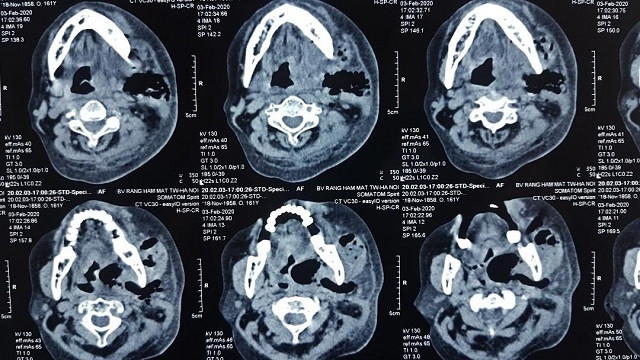

Khối mủ lớn vùng cổ dưới hàm bên T lan rộng.

Ngay khi đến Bệnh viện Hữu nghị Việt Đức, người bệnh được khẩn trương làm xét nghiệm, chụp chiếu phim với chẩn đoán bệnh viêm tấy sàn miệng lan tỏa và tiến hành mổ cấp cứu. Ca mổ tiến hành thuận lợi khi rạch vùng dưới hàm người bệnh ra hàng trăm ml mủ, ổ mủ thông vào khoang miệng, lan xuống vùng cổ và có nguy cơ lan trung thất nếu không được xử lý kịp thời. Hiện người bệnh còn ống nội khí quản nhưng tỉnh hoàn toàn, hết sốt, có dẫn lưu và hệ thống rửa liên tục mủ vùng ổ áp xe, kết hợp kháng sinh mạnh liều cao và hồi sức. Da vùng dưới hàm cổ được rạch rộng để mở và dự kiến sẽ khép lại sau từ 7-10 ngày.